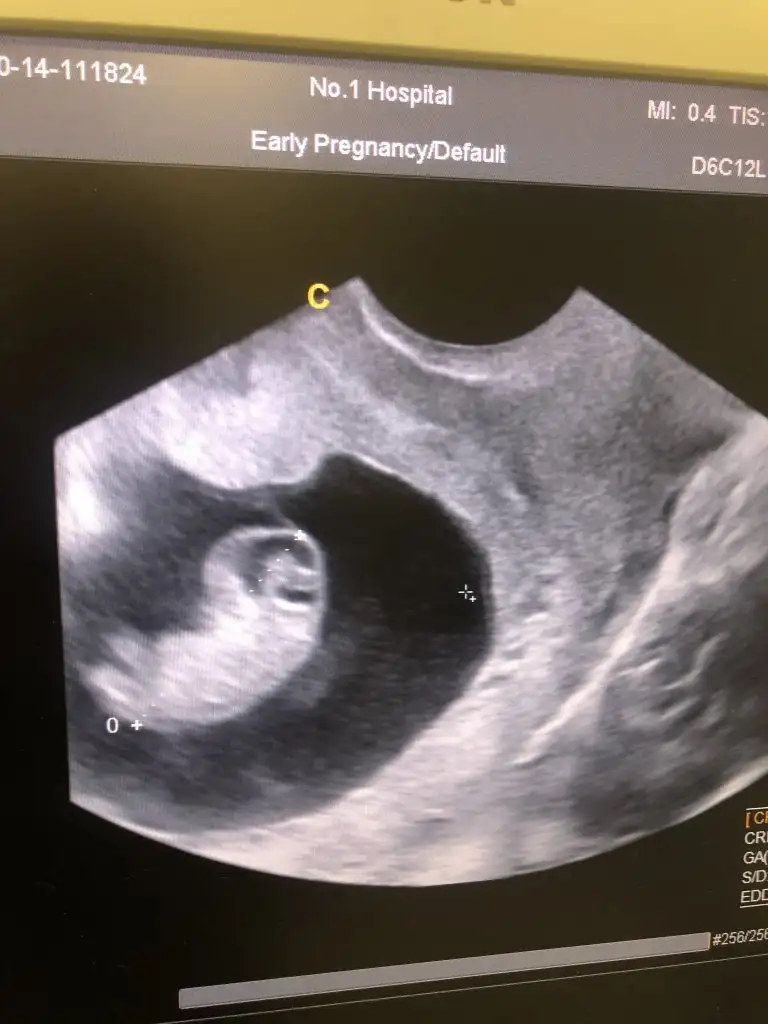

9+1 kahverengi aktıntım oldu panikledım acil e gittim çok şükür herşey yollunda umarım böyle devam eder iki düşük geçmişim var çok korkuyorum . Umarım herkes iyidir sağlıkla gelsin inşallah 🤍

Eklentiler

• 681147EE-0C88-46A0-870F-5AD8100F746B.webp

681147EE-0C88-46A0-870F-5AD8100F746B.webp

28,9 KB · Görüntüleme: 45